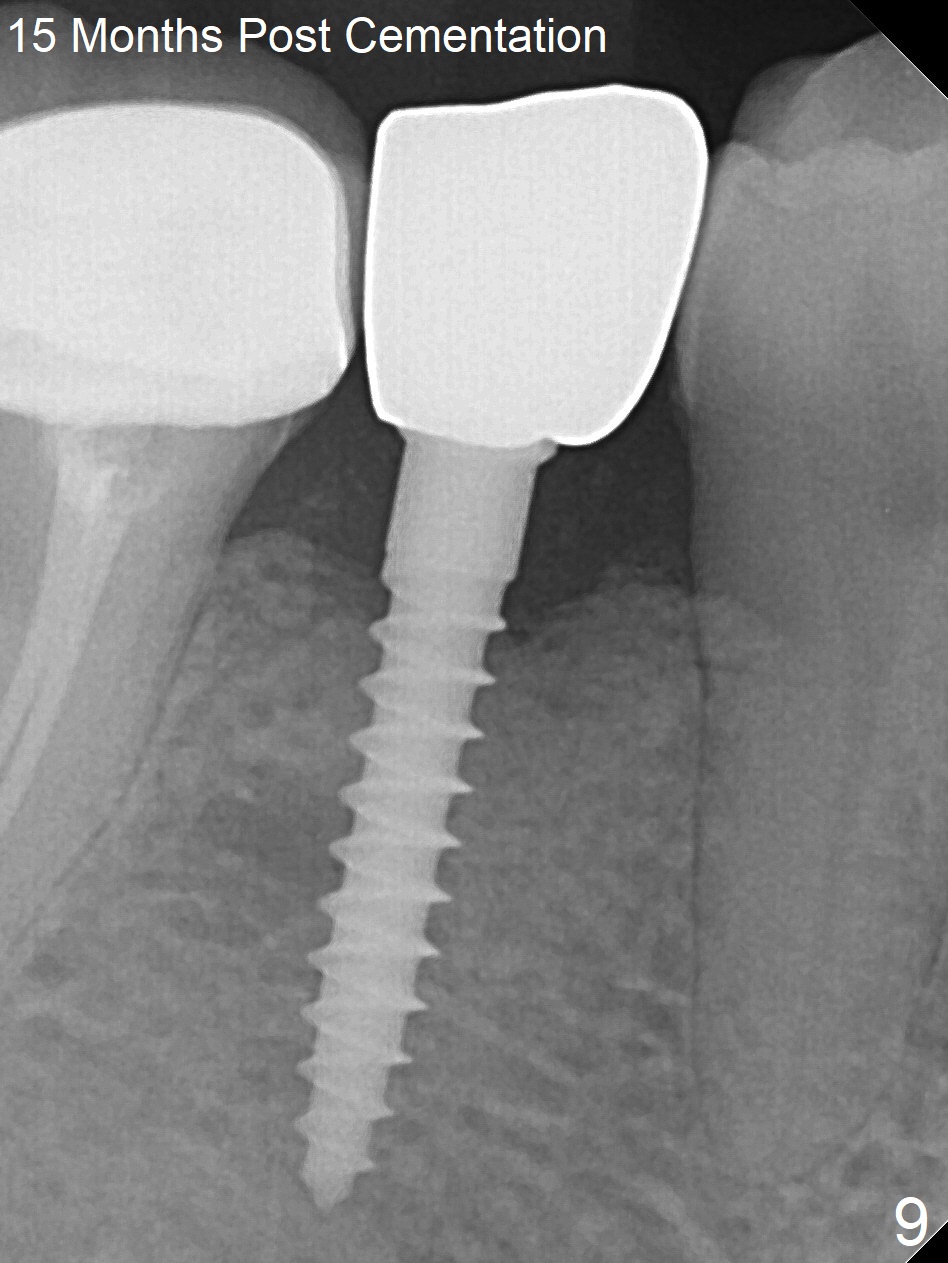

Preop photo shows the distal inclination of the tooth #28 (Fig.1). The distal surface of the latter is reduced before incision for implant placement at #29 (Fig.2). The buccolingual width is approximately 4 mm, as compared to 3 mm implant positioner (Fig.3). After 1.2x10 mm osteotomy (Fig.5), the mesiodistal cortical bone is removed with a small high-speed fissural bur (Fig.4). When a 2.5x12(2) mm 1-piece implant is placed (Fig.6), there is no buccal (Fig.7) or lingual plate perforation. There is no postop paresthesia. There is mild bone loss distal 4 months postop (Fig.8 *). Take photos before and after permanent crown cementation to show increase in ridge width after bone graft and improvement in gingival health after provisional modification. Take PA and/or BW post cementation to show that the distal bone resorption (Fig.8 *) is partially due to angulation. No continuous bone loss 15 months post cementation (Fig.9). There is mild bone resorption mesially 2 years 3 months post cementation (Fig.10). The soft and hard tissues remain healthy 4 years 3 months post cementation (Fig.11,12).